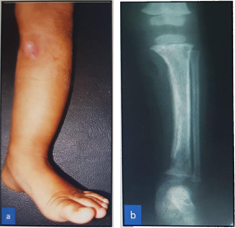

Case - 1

Before

After